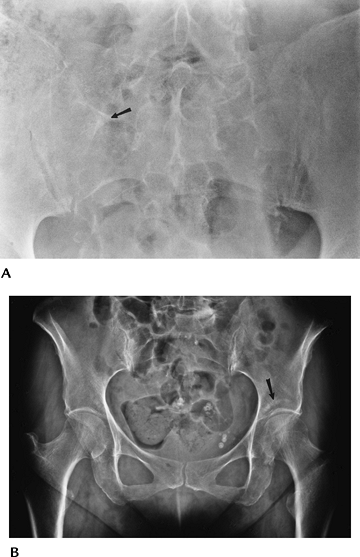

FIGURE 4-37 Osteoid osteoma. (A) Routine radiographs demonstrating medial joint space widening (arrow) caused by soft tissue reaction. (B) Axial T2-weighted MR image showing focal increased signal along the femoral neck (arrow). (C) CT clearly demonstrating osteoid osteoma (arrow). Note the anterior soft tissue thickening (open arrow).

|